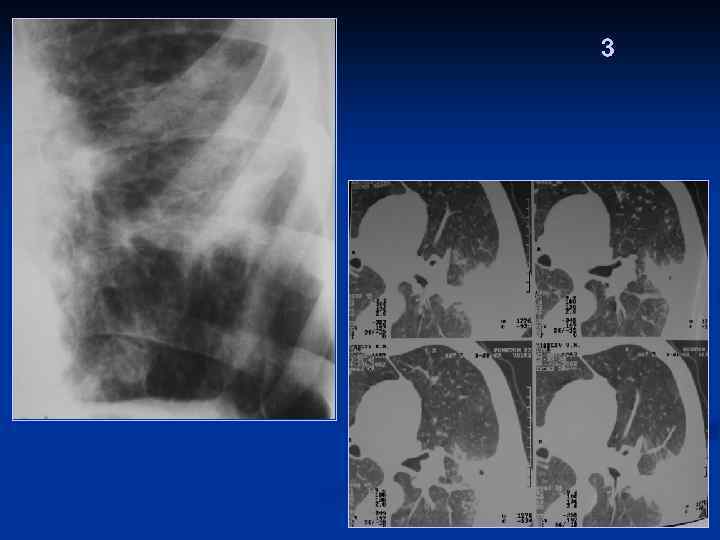

3 Пациентка 48 лет, с аспириновой астмой , длительным анамнезом приема ГКС. Внутрибольничная септическая «ПН»

Внутрибольничная септическая «ПН»

Септическая «ПН» Динамика

3